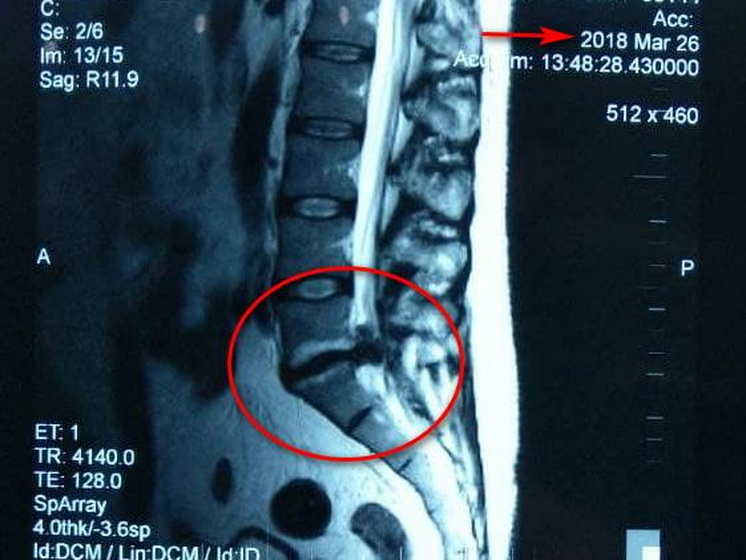

Нещодавно до мене прийшов мій пацієнт на повторний огляд, у якого у 2018 році була діагностована секвестрована кила хребта, яка підлягала оперативному втручанню. Медикаментозне лікування не приносило полегшення. Ми підібрали йому курс комплексного лікування на 20 днів. Повторне МРТ показало, що кила зникла, лишилася лише протрузія, яку ми також успішно пролікували», - розповідає Валентина Яцук, лікар вертебролог центру.